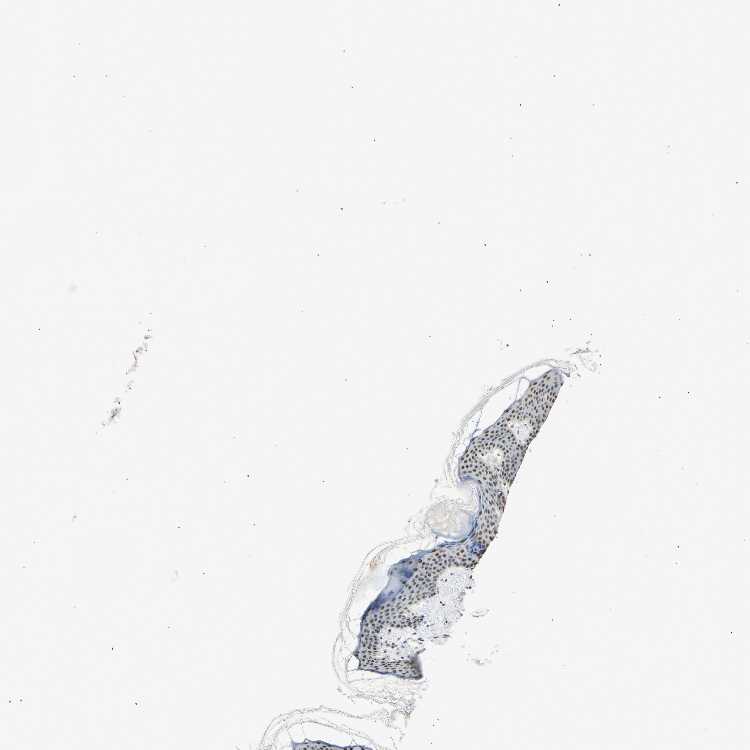

TISSUE PRIMARY DATA SKIN Show tissue menu

SKIN 1 - Antibody stainingi

Antibody staining in the annotated cell types in the current human tissue is reported as not detected, low, medium, or high, based on conventional immunohistochemistry profiling in selected tissues. This score is based on the combination of the staining intensity and fraction of stained cells.

Each image is clickable and will lead to virtual microscopy that enables deeper exploration of all samples and also displays staining intensity scores, fraction scores and subcellular localization as well as patient and tissue information for each sample.

Antibody HPA008751Antibody CAB005227

Langerhans -Low

Cells in basal layer Medium-

Cells in corneal layer Not detected-

Cells in granular layer Medium-

Cells in spinous layer Medium-

Endothelial cells Medium-

Extracellular matrix Not detected-

Fibroblasts -Low

Fibrohistiocytic cells Medium-

Keratinocytes -Low

Langerhans cells Medium-

Lymphocytes Medium-

Melanocytes LowLow

Vascular mural cells Not detected-